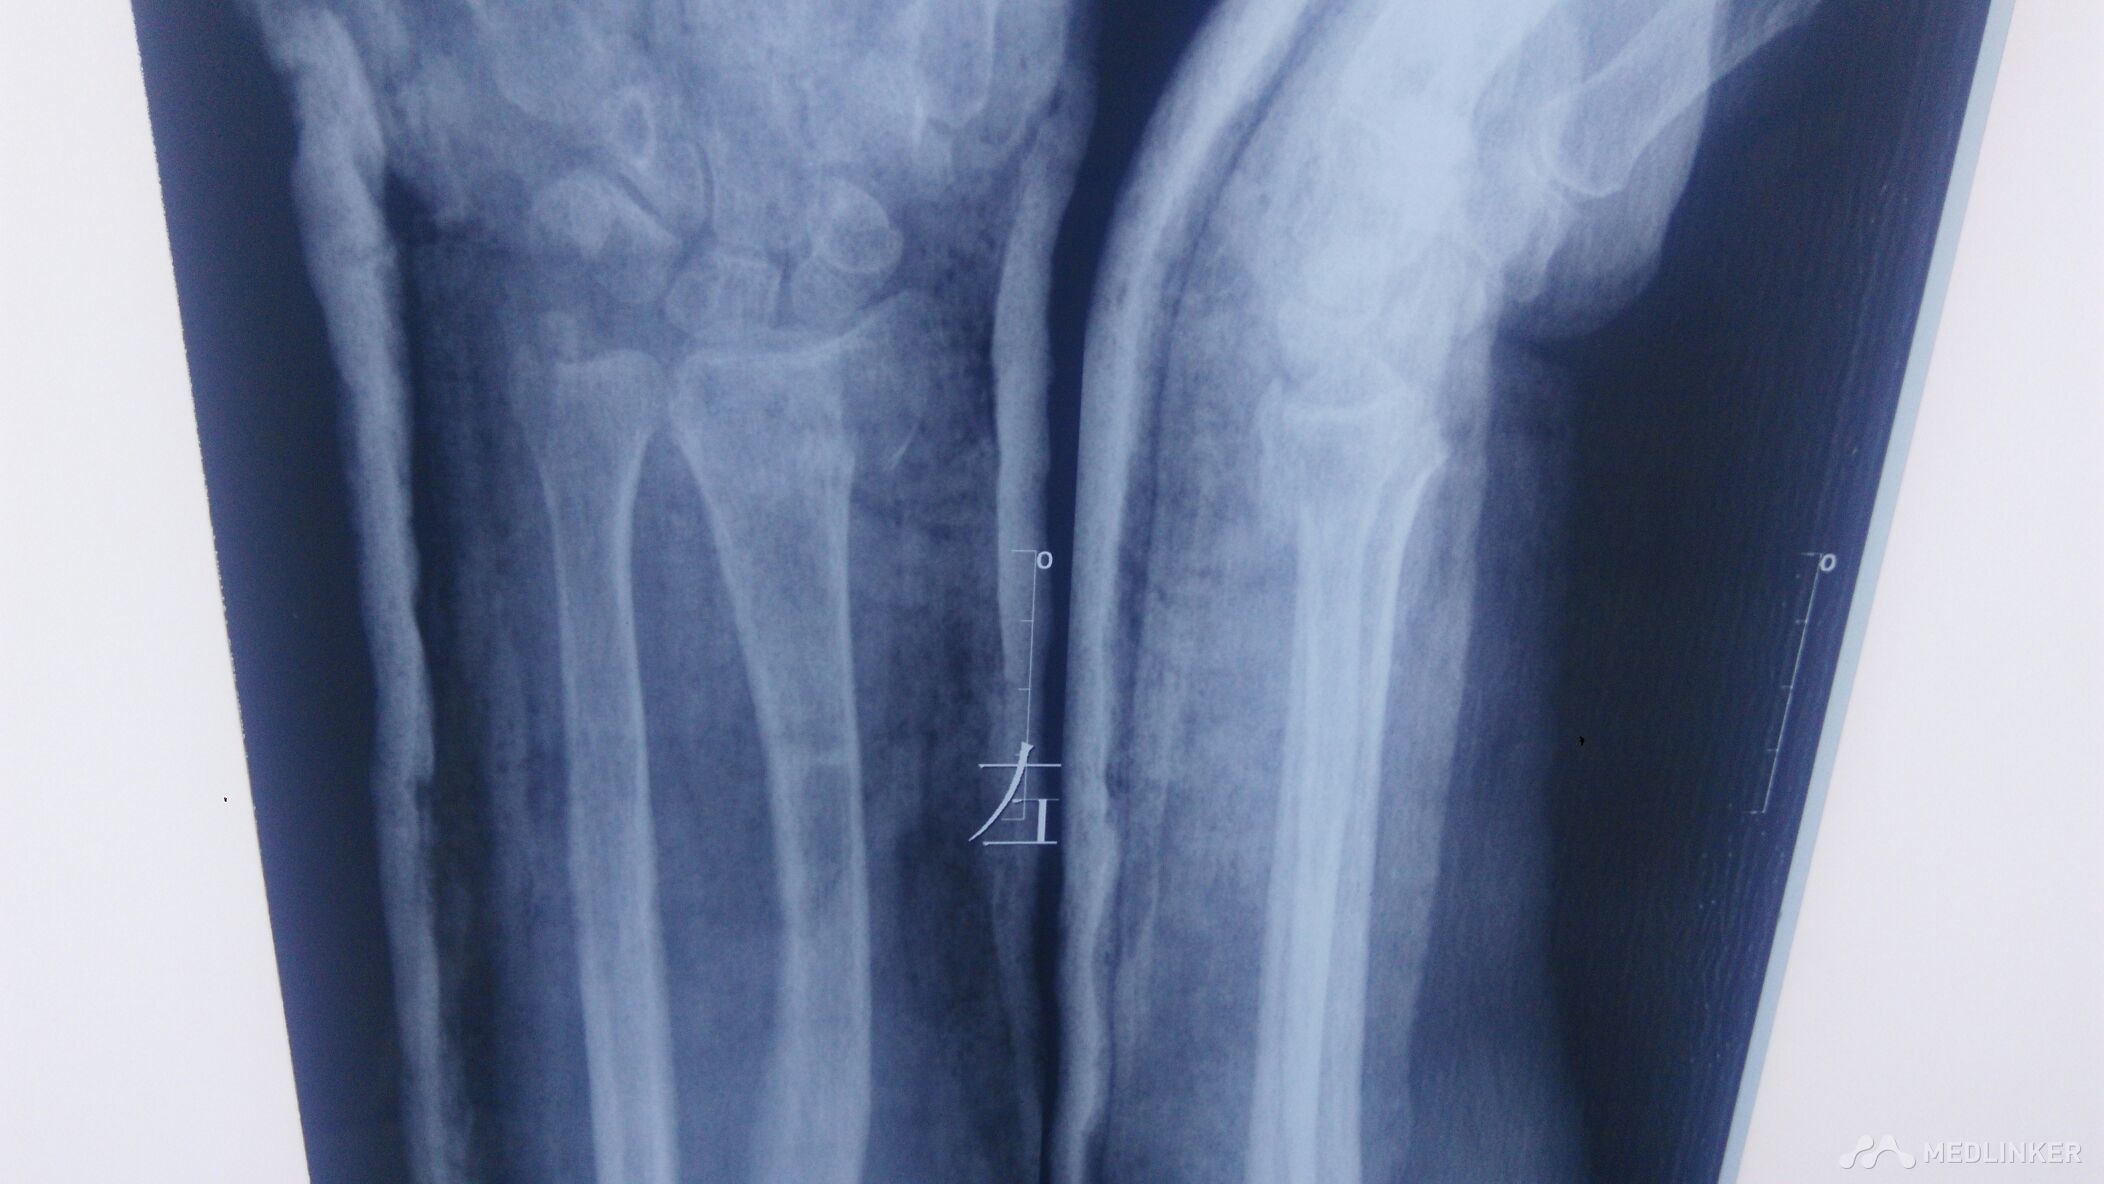

左桡骨远端骨折,左尺骨茎突骨折。

左腕部外伤后,血压高压210.低压110.左腕疼痛,畸形明显。手法复位。

左腕部外伤后,畸形明显伴疼痛。左手末梢感觉麻木。左腕部活动受限。

左桡骨远端骨折,左尺骨茎突骨折,手术治疗。

已经尽力了。尺偏,北侧仍然移位。血压太高。不手术治疗,不行啊!家属不愿手术治疗。怎么办?